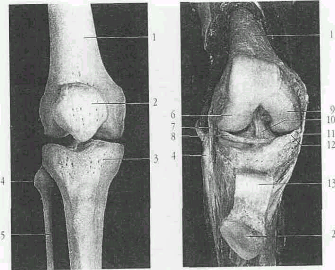

Рис.2 Костные элементы коленного сустава. Правый коленный сустав.

1 - бедренная кость;

2 - надколенник;

3 - большеберцовая кость;

4 - головка малоберцовой кости;

5 - малоберцовая кость;

6 - боковой (латеральный) мыщелок.;

7 - наружная боковая связка коленного сустава;

8 - латеральный мениск (межсуставной хрящ коленного сустава);

9 - медиальный мыщелок коленного сустава;

10 - передняя крестовидная связка;

11 - внутренняя боковая связка коленного сустава;

12 - внутренний мениск (промежуточный диск коленного сустава;

13 - связка надколенника.

Внутри сустава расположены две мощные крестообразные связки колена. Капсула начинается в виде дуги на 0,5-1 см выше края хрящевой поверхности бедра, образуя впереди верхний заворот, переходит через сустав и прикрепляется к менискам, образуя боковые завороты. Спускается вниз и прикрепляется к большеберцовой кости, образуя передненижний заворот. Сзади капсула начинается по краю суставных поверхностей мыщелков бедренной кости, срастается с менисками и прикрепляется к краю суставной поверхности большеберцовой кости. На задней поверхности образуются задневерхний, задненижний, латеральный и медиальный завороты. Внутренняя поверхность капсулы выстлана синовиальным слоем, который с обеих сторон надколенника образует синовиальные крыловидные складки, включающие жировую клетчатку.

Рис 4. Правый коленный сустав вид сзади

13 - связка надколенника;

14. - задняя крестообразная связка.